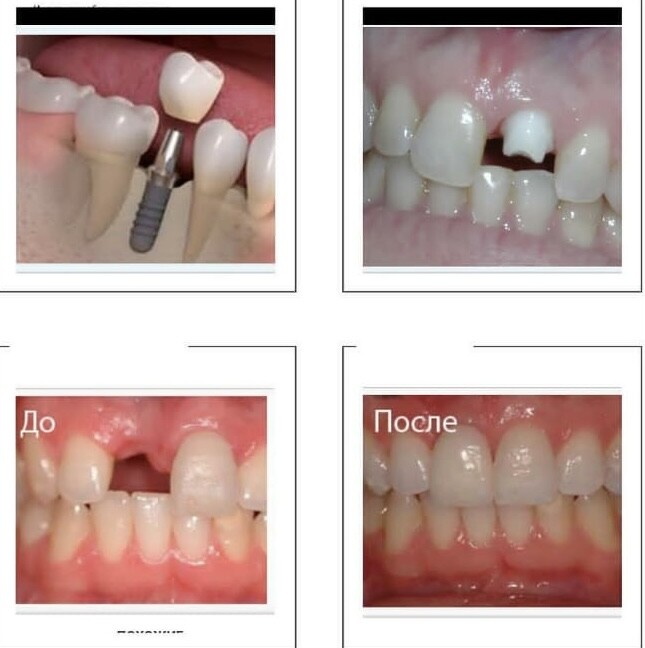

Имплантация зубов

Одномоментная имплантация

Имплантация по 3D шаблону

Имплантация Al-on-4

Протезирование зубов

Зубные коронки

Протезирование

Протезирование на имплантах

Имплантация – один из методов восстановления отсутствующих зубов в зубном ряду, сохраняющий внешний вид и жевательную способность челюсти.